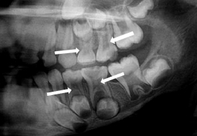

Çoklu pulpa taşlarının radyografisi. [Image credit: “OPG revealing pulp stones and taurodontism in all primary molars” by Mohita Marwaha et al, Case Reports in Dentistry is licensed under CC BY 4.0 / cropped]

Vücudun başka yerlerinde bağ dokusunun hasar görmesi yara dokusu oluşumuna yol açabilir. Ancak pulpada odontoblastların varlığı skar dokusunun mineralize olmasına neden olur. Kalsifiye skar dokusu oluşumu vücudun başka yerlerinde Distrofik kalsifikasyon olarak bilinen nadir bir durumdur, ancak pulpada yaygındır. Pulpadaki lokalize kalsifikasyon bölgelerine pulpa taşları (veya dentiküller) denir. Bunlar hem radiküler pulpada hem de koronal pulpada görülür. Pulpa taşlarının klinik açıdan en büyük önemi, endodontik tedaviyi zorlaştırabilmeleridir. Pulpa taşları sadece pulpada (serbest) bulunmaz, aynı zamanda dentin üzerinde (yapışık) ve dentin içinde (gömülü) de görülebilir.